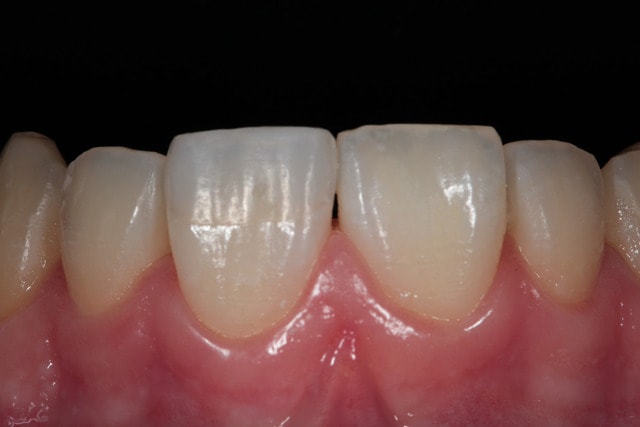

Petit retour nostalgique sur ce fil, suite au passage en contrôle (2 ans après), d'une gamine de 14 ans maintenant qui s'était bousillé la 11 dans la cour de récrée. C'est toujours du GC et du Rénamel (Light, et pour le coup un poil trop clair), et ça vieillit bien (ça va rassurer Maz).

mg 8321 itysqh - Eugenol

mg 8323 mykrrf - Eugenol

mg 8337 gvk66r - Eugenol

mg 8338 fghgau - Eugenol